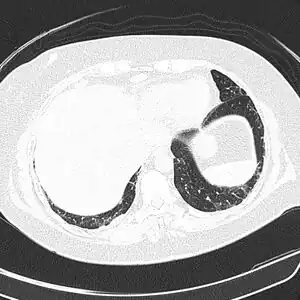

CT scan lungs: mass in right upper lobe -